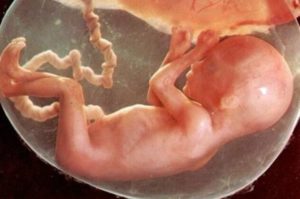

Что происходит с ребенком

Плод активно развивается и совершенствуется. Его размер достигает 25 см, а масса составляет примерно 350 граммов. Внутренние органы и системы продолжают развиваться. Организм готовится к автономному существованию – особенно стремительно развиваются нервная система и головной мозг.

Некоторые из органов уже почти полностью сформировались: малыш слышит происходящее вокруг, чувствует свет. Обоняние и осязание также работают.

Активное развитие головного мозга и нервной системы приводит к тому, что движения малыша становятся более скоординированными, он начинает реагировать на какие-либо ощущения. Ребенок уже может улыбаться, зевать, глотать.

Плод на 19 неделе уже имеет полностью сформированный скелет. Хрящи укрепляются, конечности становятся более пропорциональными. Кожа еще тонкая и красная, вся в морщинках, но совсем скоро под ней начнет скапливаться слой подкожного жира, что приведет к разглаживанию складок.

Органы пищеварения сформированы и готовятся к тому, что в скором времени они начнут работать самостоятельно и в полную силу. Почки уже включены в деятельность – выводят мочу.

Не в полной мере еще сформированы легкие, но и они скоро будут готовы к тому, чтобы работать самостоятельно.